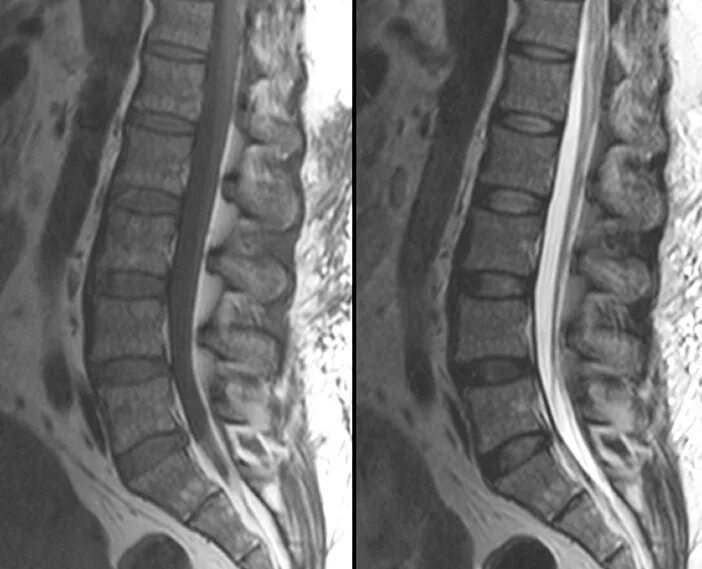

Spine mri